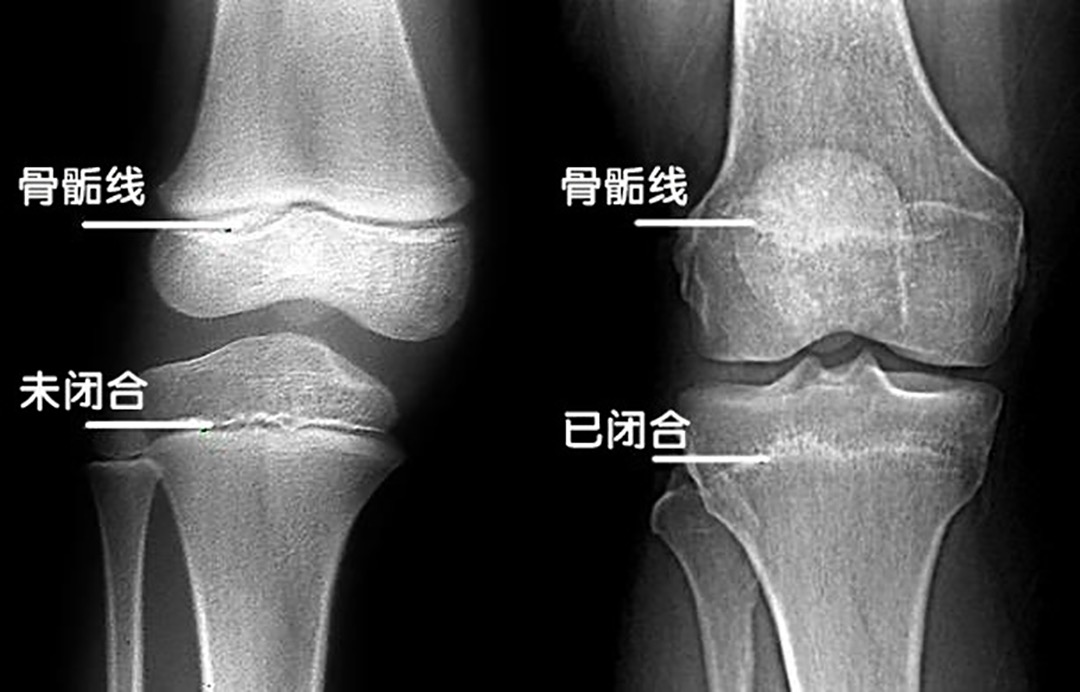

成年人一旦身高定型之后,就再也不可能长高了。因为人是否还能长高,取决于我们大腿骨和小腿骨之间的骨骺线有没有闭合,如果骨骺线中间有软骨垫着,使这里的骨骺线没有闭合的话,就还有长高的机会,但是如果闭合了,那就可以说是定型了。而这个骨骺线中间的软骨一般在成年后就会消失,骨骺线也会因此闭合,这个闭合的时间也是由基因决定。所以,只要是成年人,想要通过训练长高,基本上是不可能的事情。